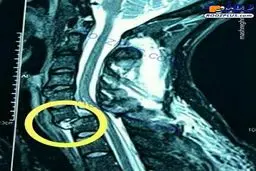

تصویری هولناک از شکستگی گردن بازیکن استقلال!